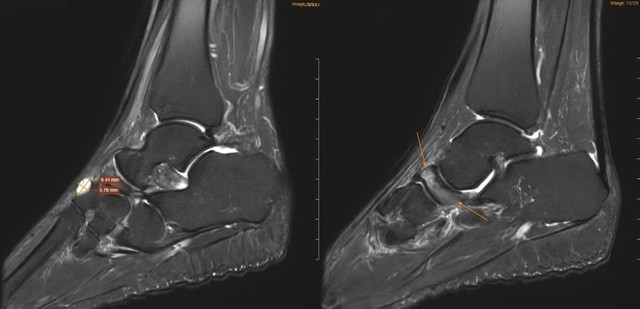

Để xác định nguyên nhân, các bác sĩ đã chỉ định chụp cộng hưởng từ (MRI). Kết quả cho thấy xương ghe bị xẹp và biến dạng điển hình hình “dấu phẩy”, kèm đặc xương dưới sụn và phù tủy xương rõ rệt. Ngoài ra, nhiều tổn thương phối hợp cũng được ghi nhận như gai xương, phù dây chằng, tràn dịch khớp cổ chân.

Dựa trên lâm sàng và hình ảnh học, bệnh nhân được chẩn đoán theo dõi Hội chứng Mueller-Weiss ở chân phải và phù tủy xương sên trái.